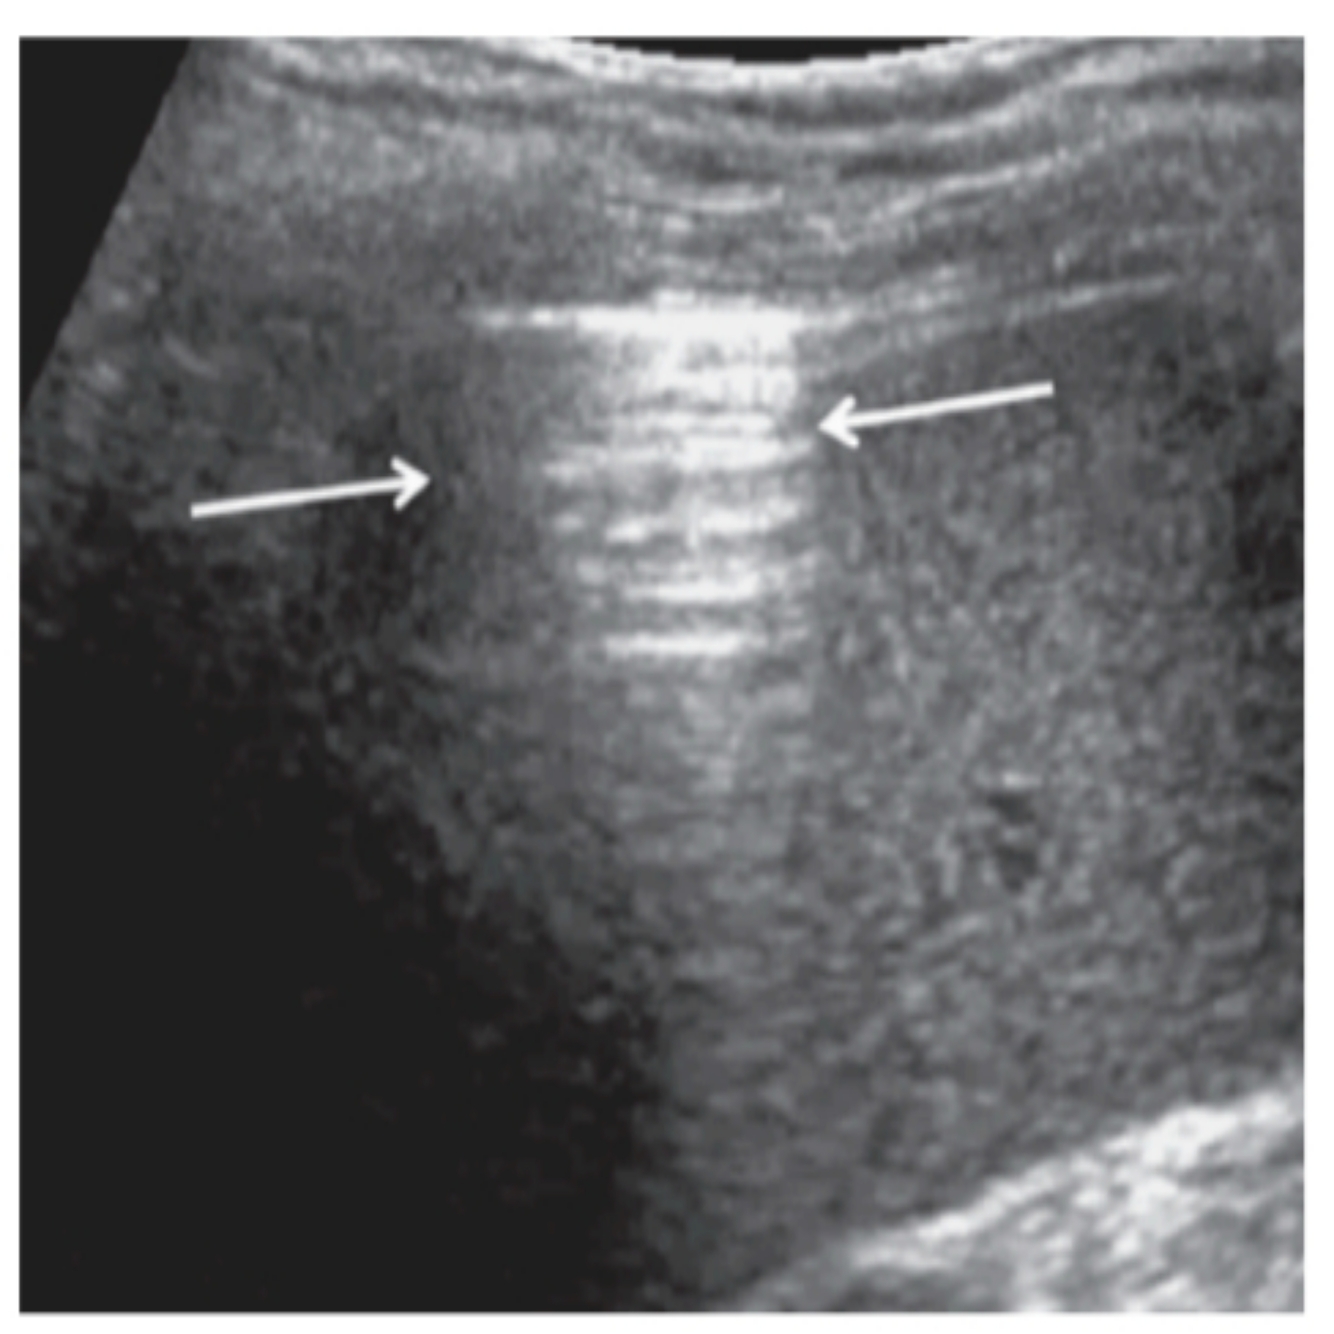

POCUS PULMONAR: Qual o nome deste achado?

Sinal do código de barras

POCUS PULMONAR: Quando as pleuras não deslizam em feixe de ponto fixo é um sinal de

Código de barras